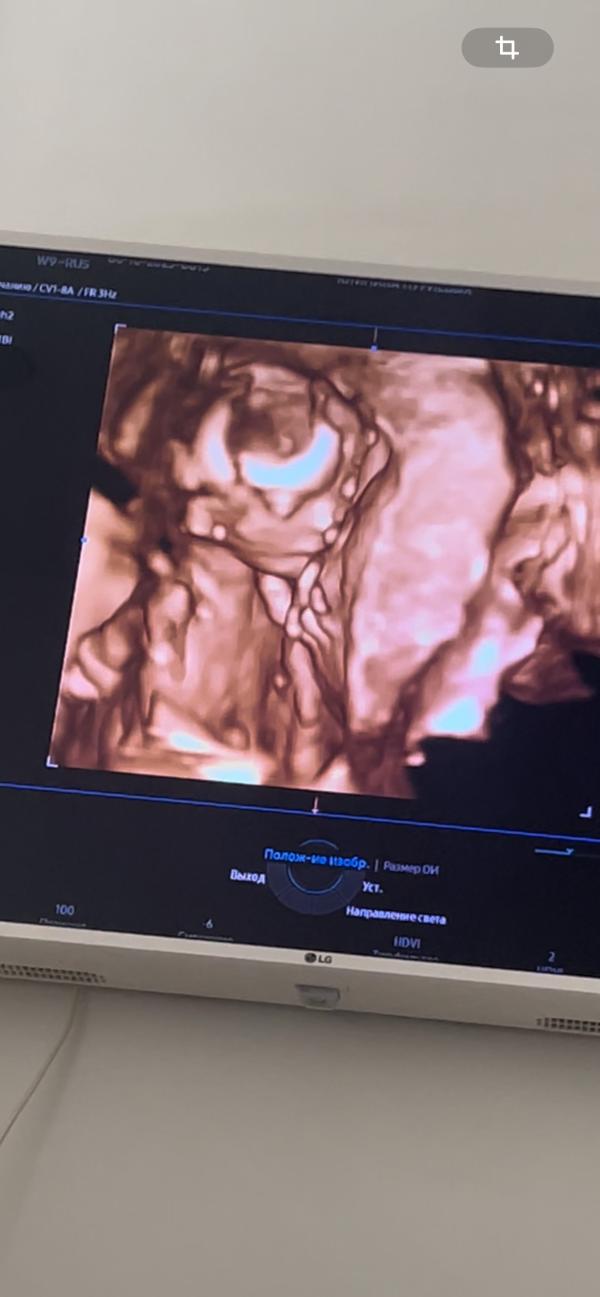

16 недель. Сделали Промежуточный скрининг и 2д узи- все хорошо. Я вижу свои черты лица 😁

Дали на раздумья 1-2 недели делать амниоцентез или нет. Генетик сказал , что он даже не смотрит биохимический скрининг, если нипт и узи хорошее . Красных флагов нет и скорее всего все у нас хорошо .